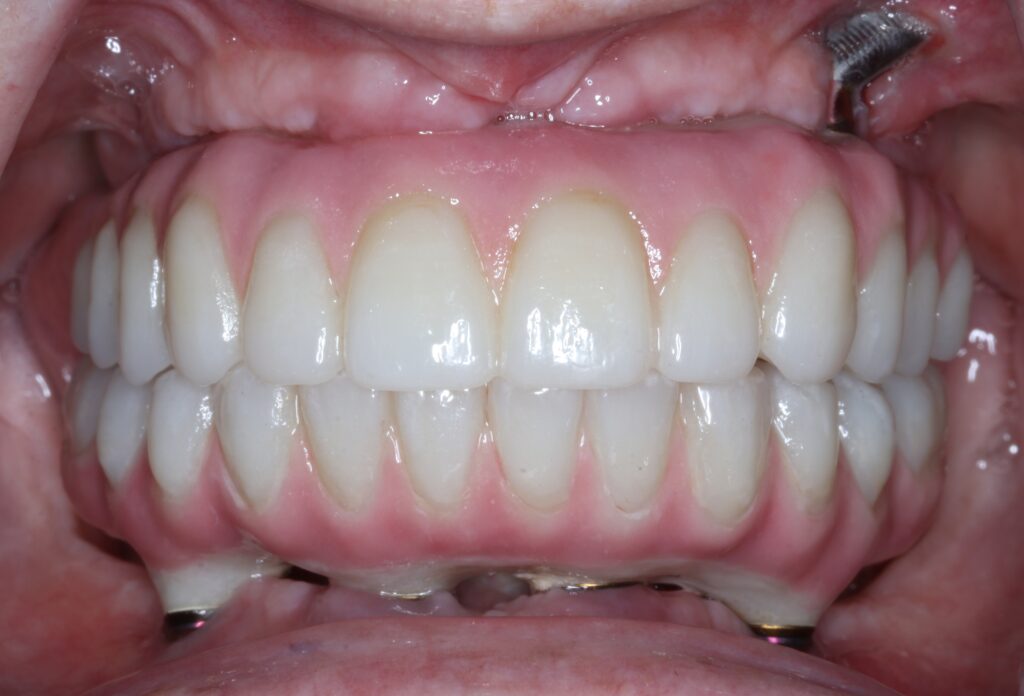

A selection of full arch fixed implant bridge patients after 5 years of wear